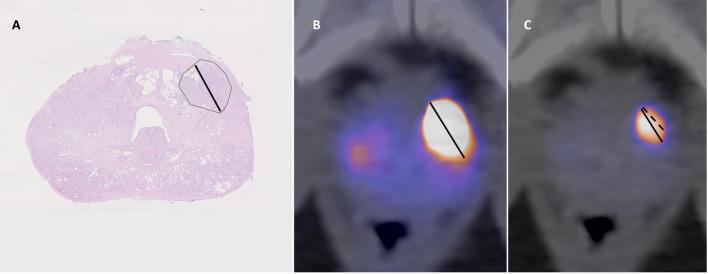

Positron emission tomography/computed tomography (PET/CT) with prostate specific membrane antigen ligands (PSMA) is established for use in primary staging of prostate cancer to screen for metastases. It has also shown promise in local tumor staging, including detection of extraprostatic extension (EPE) and seminal vesicle invasion (SVI). Previous studies have shown high heterogeneity in methods and results. Our aim was to compare [F]PSMA-1007 PET/CT to magnetic resonance imaging (MRI) in evaluation of EPE and SVI, building on a previously described method for standardized evaluation. We retrospectively included 124 patients who had undergone MRI, PSMA PET/CT and prostatectomy. PSMA PET/CT images were evaluated by two nuclear medicine physicians. Using a standardized method, they measured length of capsular contact (LCC) and assessed EPE and SVI visually with the use of 5-point Likert scales. A radiologist evaluated MRI images using criteria based on Prostate Imaging-Reporting and Data System version and incorporating LCC measurement and Likert scales. We evaluated diagnostic performance with histopathology as reference, and the interrater reliability of the PET evaluations.

The sensitivity and specificity for detecting EPE with the quantitative LCC method for PSMA PET/CT was 0.46/0.91, for the visual method 0.28/0.82 and for the combination of the two 0.54/0.76. AUC in ROC analysis for the LCC method was 0.70. For MRI the sensitivity and specificity were 0.80/0.64. For SVI, PET/CT and MRI had sensitivity and specificity of 0.14/1.0 and 0.50/0.92 respectively. The intraclass correlation coefficient for the PET LCC measurement was 0.68, the kappa values for the visual Likert scales for PET were 0.53 for EPE and 0.63 for SVI.

正电子发射断层扫描/计算机断层扫描(PET/CT)联合前列腺特异性膜抗原配体(PSMA)已被用于前列腺癌的初始分期以筛查转移灶。它在局部肿瘤分期方面也显示出前景,包括检测前列腺外侵犯(EPE)和精囊侵犯(SVI)。既往研究表明方法和结果存在高度异质性。我们的目的是在先前描述的标准化评估方法基础上,比较[F]PSMA - 1007 PET/CT与磁共振成像(MRI)在评估EPE和SVI方面的差异。我们回顾性纳入了124例接受过MRI、PSMA PET/CT和前列腺切除术的患者。PSMA PET/CT图像由两名核医学医师评估。他们使用标准化方法测量包膜接触长度(LCC),并使用5级李克特量表直观评估EPE和SVI。一名放射科医生根据前列腺影像报告和数据系统版本的标准评估MRI图像,并纳入LCC测量和李克特量表。我们以组织病理学为参考评估诊断性能,以及PET评估的评分者间信度。

PSMA PET/CT定量LCC法检测EPE的敏感性和特异性分别为0.46/0.91;视觉法为0.28/0.82;两者结合为0.54/0.76。LCC法在ROC分析中的AUC为0.70。MRI检测EPE的敏感性和特异性分别为0.80/0.64。对于SVI,PET/CT和MRI的敏感性和特异性分别为0.14/1.0和0.50/0.92。PET LCC测量的组内相关系数为0.68,PET视觉李克特量表评估EPE的kappa值为0.53,评估SVI的kappa值为0.63。